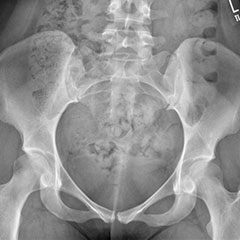

DDH (Hip Dysplasia)

Developmental dysplasia of the hip (DDH) is the most common paediatric hip condition. Abnormal hip development in the womb leads to a joint that can be unstable or even dislocated at birth. Children may present with a leg length discrepancy, restricted abduction, abnormal gait (walking) or even signs of instability. This can be missed, especially if both sides are affected. Earlier treatment is less invasive and more effective.

Dysplastic hips on child - before

Dysplastic hips on child - after